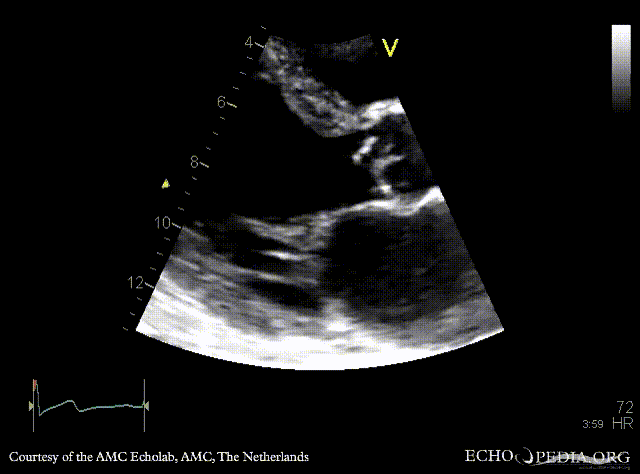

Endocarditis of aortic valve

PLAX: vegetations on aortic valve, dilated left ventricle and left atrium PLAX: Color Doppler, severe aortic regurgitation, excentric jet, and moderate mitral regurgitation